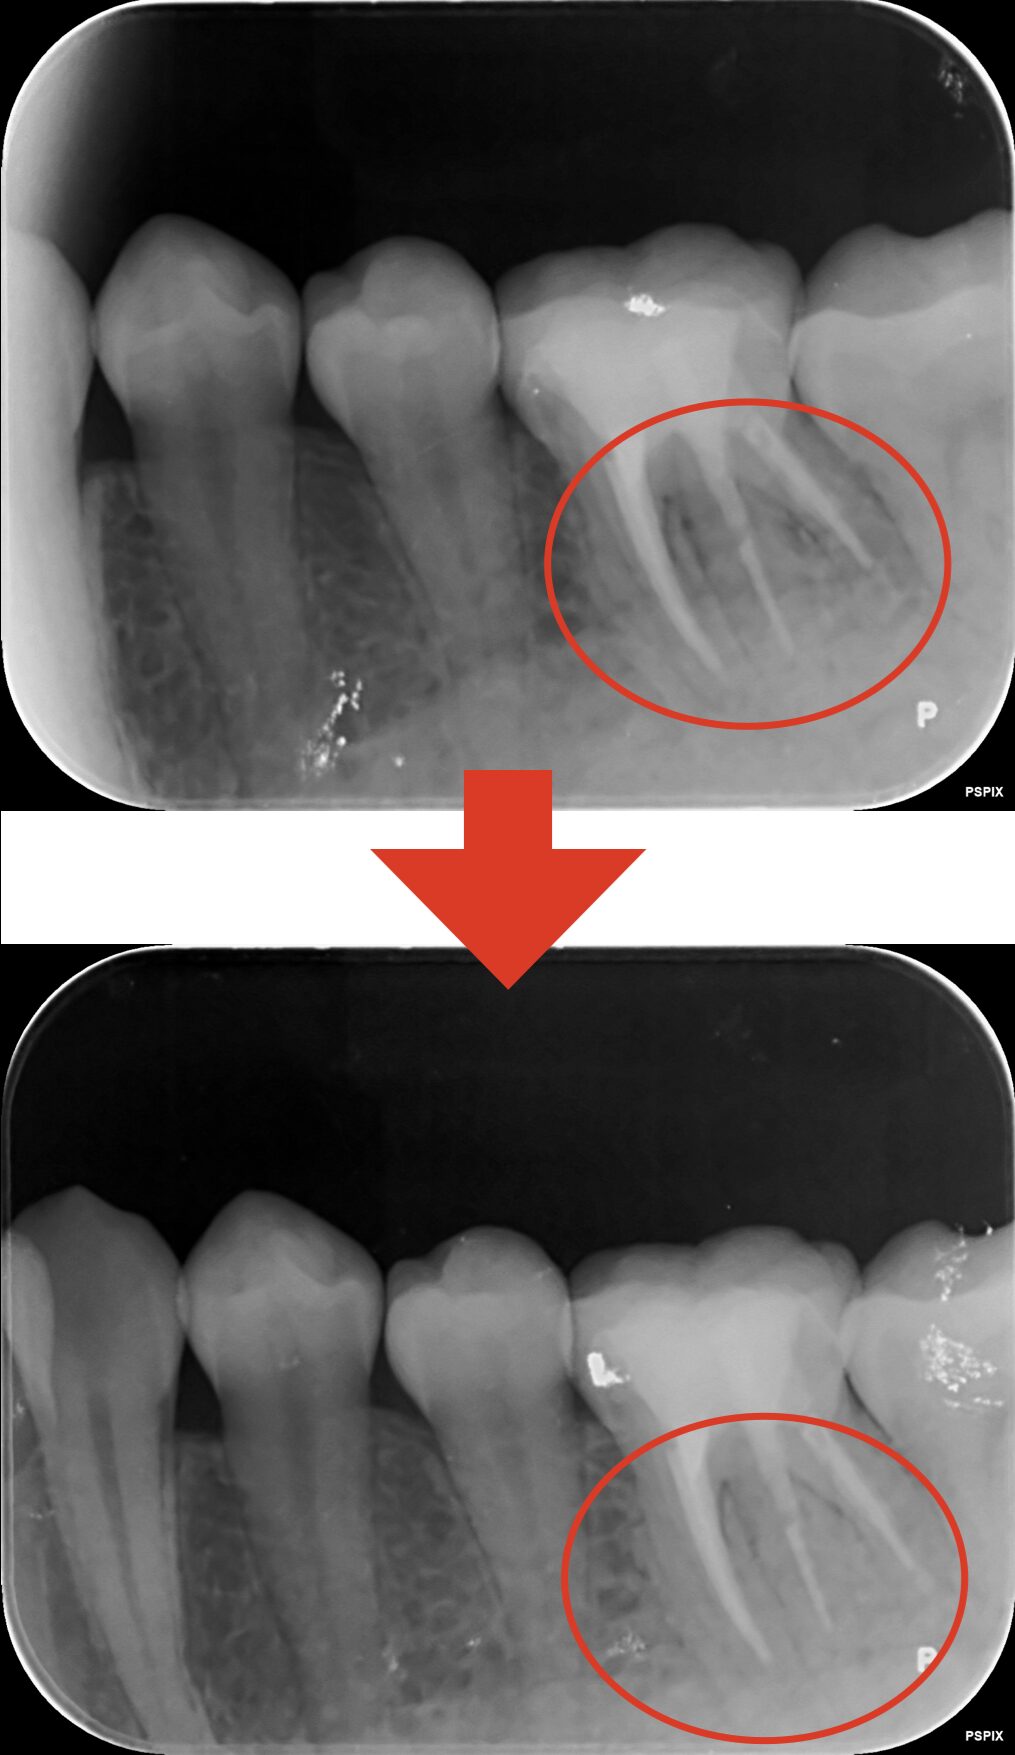

神経を抜いたのに痛む歯を当院で治療した症例

患者様は他院で何度も根管治療を行い、すでに神経は抜いていましたが(抜髄)、その後も痛みが取れないことを主訴に来院されました。

当院でラバーダム防湿を行いマイクロスコープを使用して根管治療を1度行った後より、痛みの消失が認められたため、根管治療を終了し、被せ物の治療を行わせていただきました。